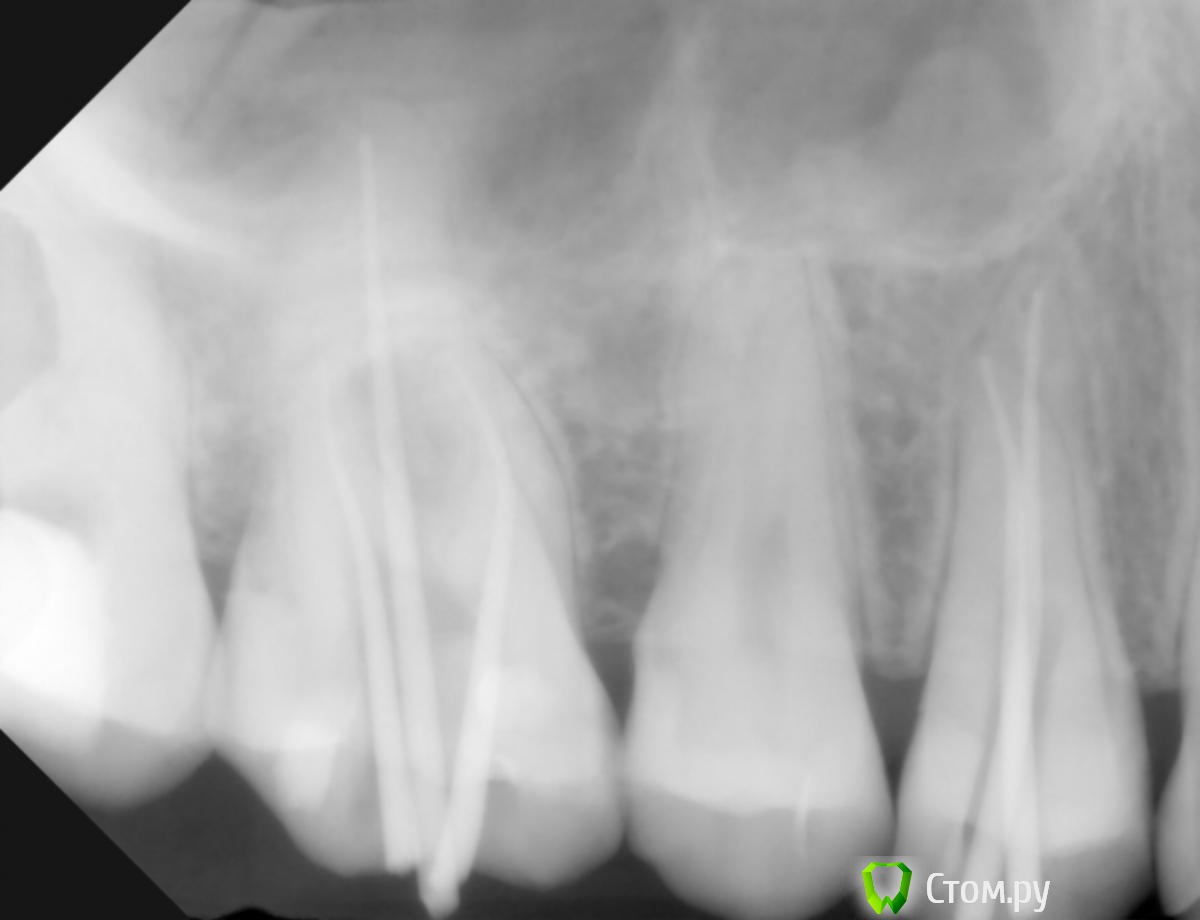

M@estro Опубликовано 17 апреля, 2014 Поделиться Опубликовано 17 апреля, 2014 (изменено) Юля, добрый вечер. Снимок со штифтами,который Вы предоставили,говорит о том,что лечение проходило,с большой долей вероятности,без коффердама. Это косвенно говорит о том,что врач мог и не увидеть (и не особо искать) 4 канал. Сделайте КТ. Изменено 17 апреля, 2014 пользователем M@estro Ссылка на комментарий

Юлия Арт Опубликовано 18 апреля, 2014 Автор Поделиться Опубликовано 18 апреля, 2014 Юля, добрый вечер. Снимок со штифтами,который Вы предоставили,говорит о том,что лечение проходило,с большой долей вероятности,без коффердама. Это косвенно говорит о том,что врач мог и не увидеть (и не особо искать) 4 канал. Сделайте КТ.день добрый! Коффердам использовался при лечении - забыть такую вещь во рту на зубах невозможно... я почти уверена что у меня между зубами 6 и 7 образуется киста - чувствую воспаление, на снимках его пока нет, но стоит ли ждать как говорят врачи ? КТ возможности сделать увы нет Ссылка на комментарий

Юлия Арт Опубликовано 24 апреля, 2014 Автор Поделиться Опубликовано 24 апреля, 2014 день добрый! как же непросто найти хорошего специалиста...обратилась к другому врачу - та посмотрела на снимки и сказала что может быть 4-й канал, искала его долго, но нашла!совсем маленький с полуживым нервом - пролечила, боль мучившая меня так долго-ушла!!! благодарю всех за мнение и советы! 1 Ссылка на комментарий